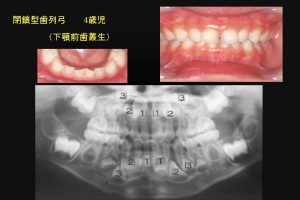

最近、乳歯の過蓋咬合の小児が増加しているような気がしてならない。(図1)

図1

図1:最近、乳歯の過蓋咬合が目立つ。